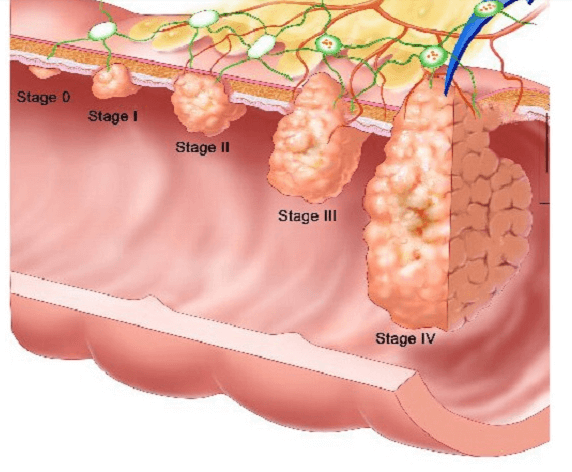

Внаслідок цього з'являються симптоми інтоксикації: нудота, запаморочення, стрибки артеріального тиску. Тріщини обростають сполучною тканиною, яка у 90% випадків перероджується в Рак.

Більше того, раніше термін переродження сполучної тканини у рак відбувався протягом 5-10 років.

За динамікою 2022 та 2023 року ми помічаємо різке скорочення цього періоду до 1-2 років. Запор на протязі 4-6 тижнів модифікує тканини в злоякісні.

Більшість симптомів раку кишечника проявляються досить явно, і їх важко не помітити. У пацієнтів із цим захворюванням на початковій стадії часто з'являються:

‘’Рак товстої кишки у жінки зі скаргою на часті запори’’

‘’Стадії раку прямої кишки які формуються протягом 1-2 років’’